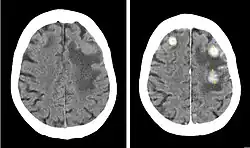

Kernstück der Diagnostik sind bildgebende Verfahren, wobei die Kernspintomographie (MRT) der Computertomographie (CT) überlegen ist.

Computertomographie

Die Computertomographie spielt als schnell durchführbares und breit verfügbares Verfahren vor allem eine Rolle in der Notfallmedizin. Größere Metastasen grenzen sich als hypodense oder selten (Malignes Melanom, Chorionkarzinom) hyperdense Struktur gegen das normale Hirnparenchym ab. Da Metastasen aber auch isodens sein können, ist womöglich nur die raumfordernde Wirkung als Massenverschiebung oder die hypodense Formation des Perifokalödems abgrenzbar. Zentrale Einblutungen, wie sie insbesondere bei Metastasen von malignen Melanomen oder Nierenzellkarzinomen vorkommen, sind in der CT gut nachweisbar. In Abhängigkeit von der gewählten Schichtdicke liegt die Nachweisgrenze bei etwa einem Zentimeter, so dass kleinere Metastasen der nativen Computertomographie entgehen können.

Da die Computertomographie einen relativ geringen Weichteilkontrast aufweist, ist die Gabe von Kontrastmittel entscheidend: aufgrund der Störung der Blut-Hirn-Schranke im Bereich der Metastase kommt es zur Anreicherung von Kontrastmittel (Enhancement), das bei Vorliegen einer zentralen Nekrose häufig ring- oder girlandenförmig erscheint.